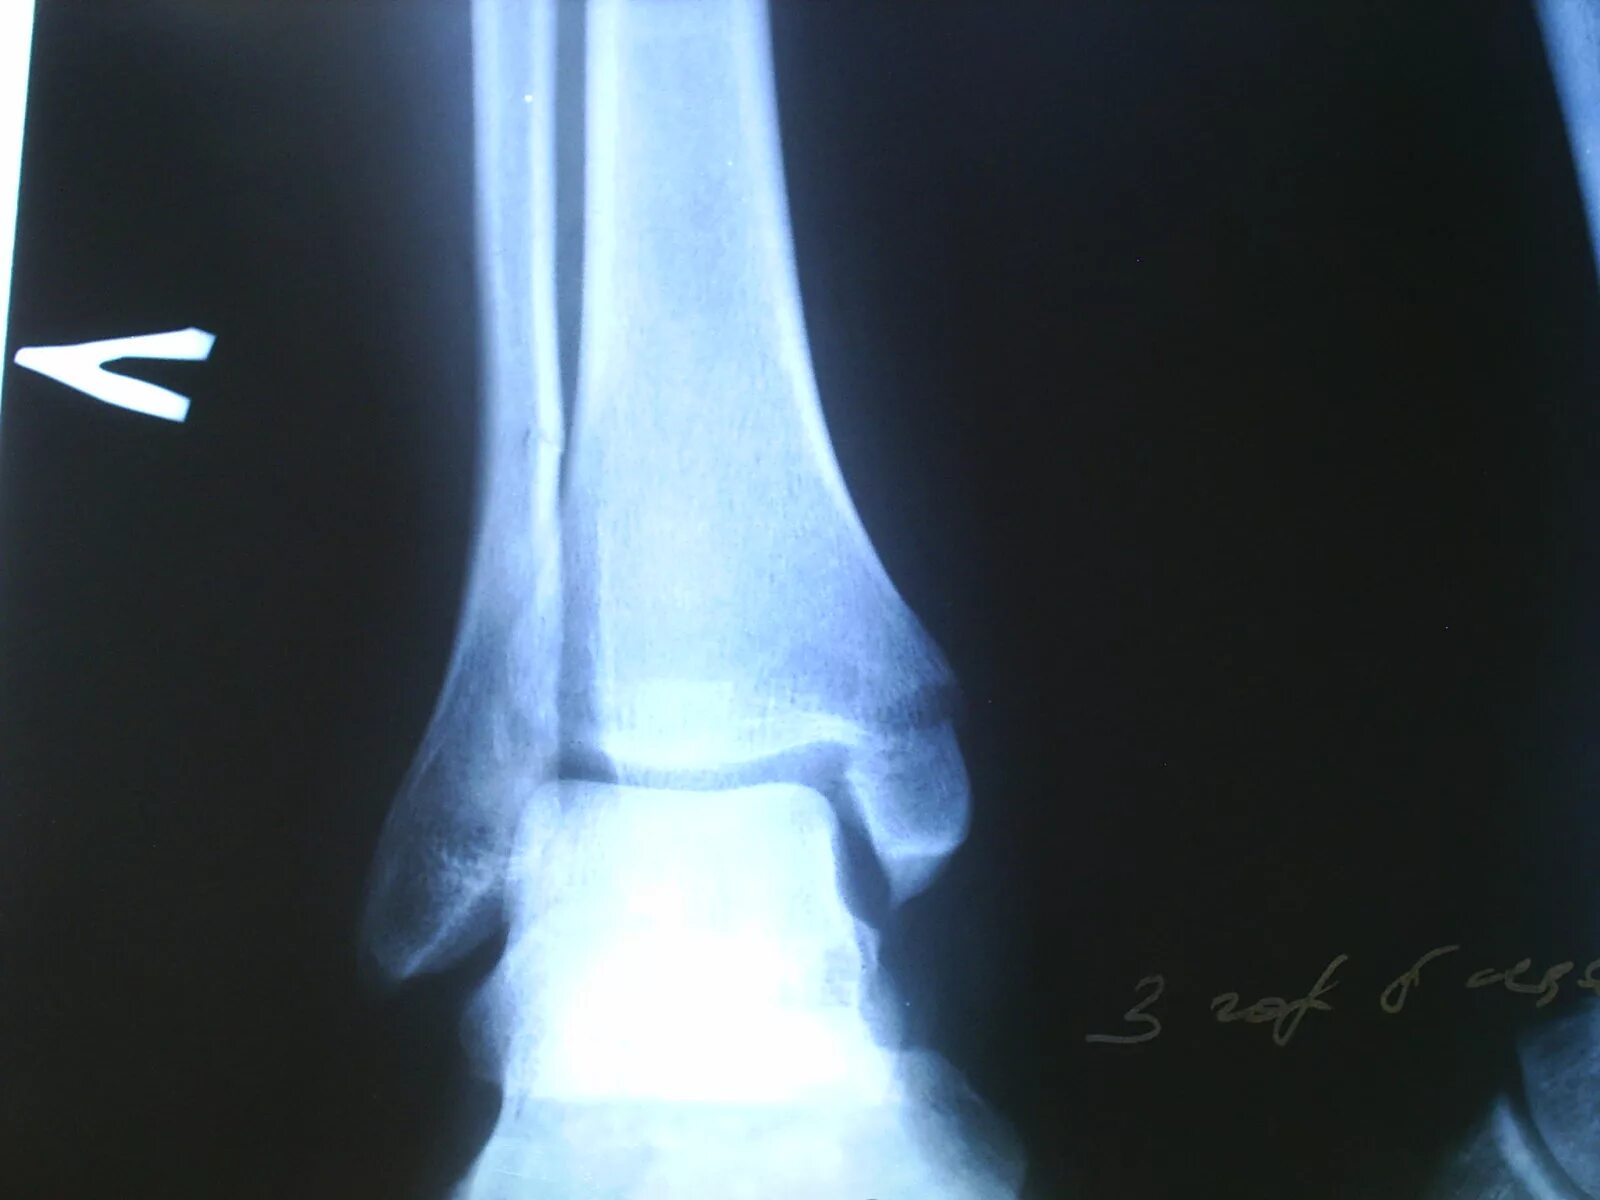

Через сколько срастается перелом лодыжки